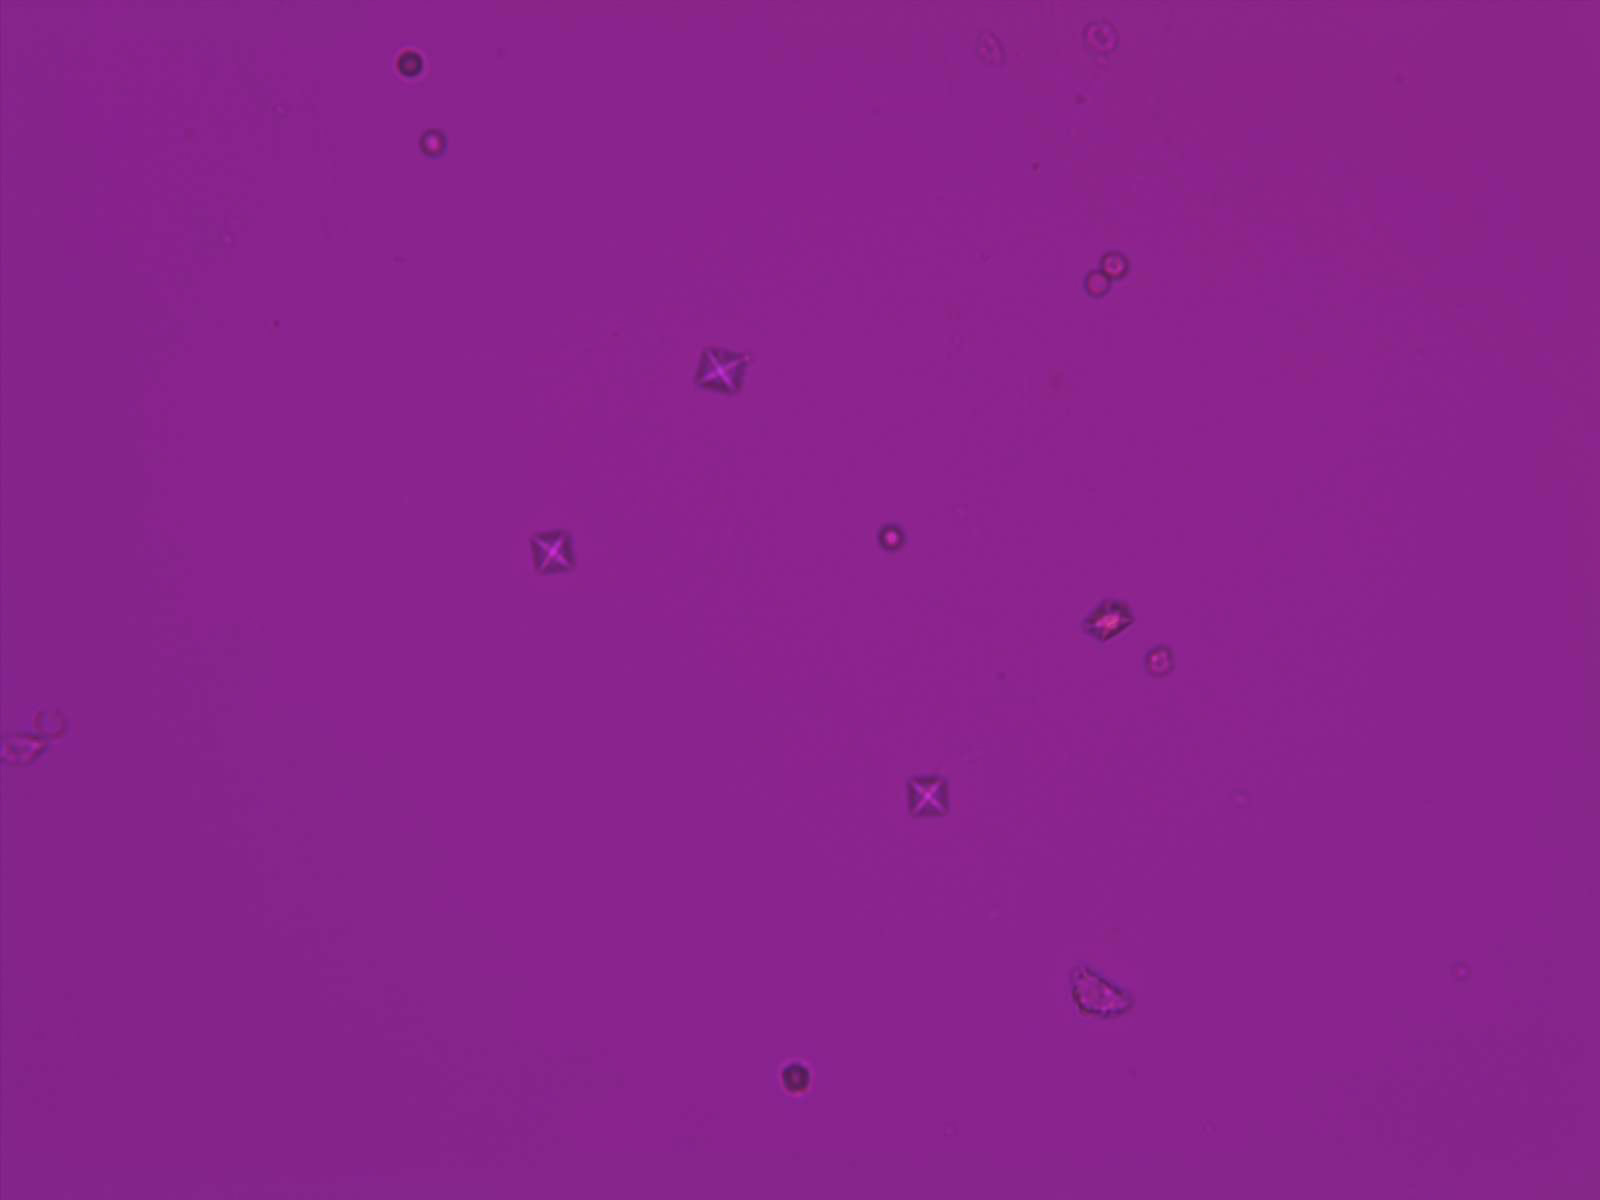

CaOx - Octahedraal

Synoniemen: Weddeliet, CaOx, CaC₂O₄·2H₂O

Calciumoxalaat dihydraat kristallen hebben karakteristieke bipyramidale of prismatische vormen. Onder de microscoop verschijnen ze vaak als envelop-vormige structuren, met een duidelijke en symmetrische morfologie. De grootte van de kristallen kan sterk variëren.

De aanwezigheid van calciumoxalaat is zelden klinisch relevant, maar kan wel een aanwijzing zijn voor de aanwezigheid van nierstenen. Ze ontstaan ook vaak in opgeslagen, oude urine. Elke vorm van calcium oxalaat is polariserend.

Overzicht